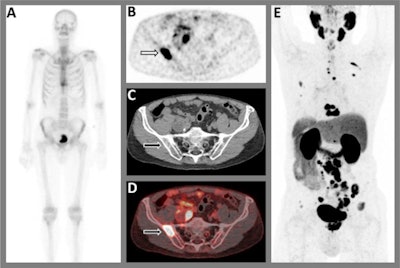

A 75-year-old patient with biopsy-proven prostate cancer. (A) Tc-99m bone scintigraphy axial images show increased bone activity in two thoracic vertebrae (Th9 and Th10) that were classified as (osteoporotic) compression fractures, and the faint uptake in the left third rib was attributed to a post-traumatic origin. Although there was a clear high-risk profile in this patient, there was no suspicion for bone metastases. (B) transversal reconstruction of F-18 PSMA-PET at pelvic region, (C) CT and (D) fused PET/CT images show a suspicion for a bone metastasis in the right iliac bone, in contrast to the bone scintigraphy. Moreover, an extensive suspicion for lymphogenous and osseous metastatic lesions were found throughout the body, as shown on (E) PET axial images. Based on the F-18 PSMA-PET/CT results, the patient was treated with androgen deprivation therapy in combination with abiraterone. Image and caption courtesy of Urologic Oncology and licensed under CC BY 4.0The researchers enrolled 79 patients with high-risk prostate cancer between March 2019 and July 2021 at two local hospitals. The patients were prospectively staged using bone scintigraphy and subsequent F-18 PSMA-PET/CT before initial therapy.

Out of 70 patients with a bone scintigraphy scan negative for metastases on primary staging, at least one bone metastasis was visualized on subsequent F-18 PSMA-PET/CT in 12.9% (9/70) of patients. In patients with low-volume metastatic disease on bone scintigraphy, upstaging to high-volume metastatic disease was reported in four of nine patients (44.4%), and downstaging to absence of bone metastatic disease in two of nine patients (22.2%), according to the findings.